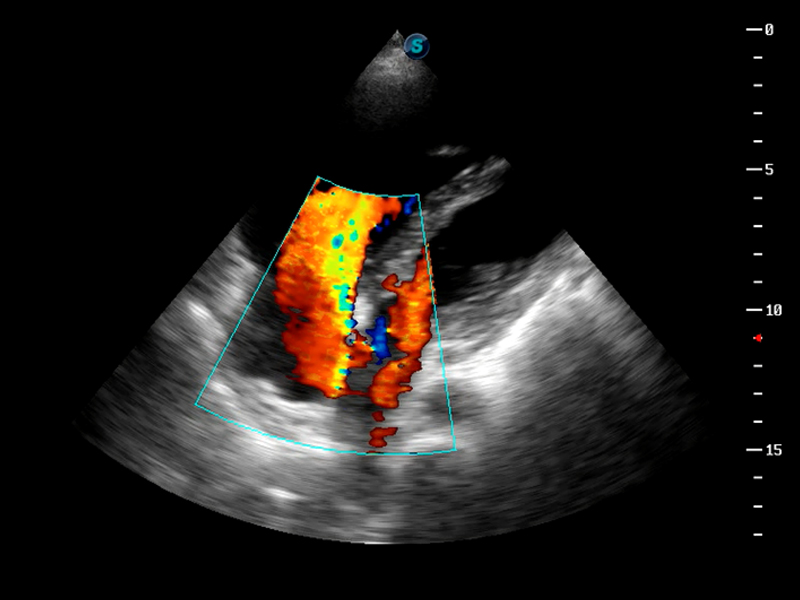

S9便携式彩色多普勒超声诊断仪是美狮贵宾会官网研发的高端便携彩超设备,外观设计新颖、产品性能卓越。S9在便携超声领域采用了突破传统的触摸屏交互设计,并以先进的软件硬件技术和设计理念,为您带来清晰的图像质量、稳定的工作性能和便捷的操作体验。

TDI组织多普勒成像

AutoC智能血流追踪